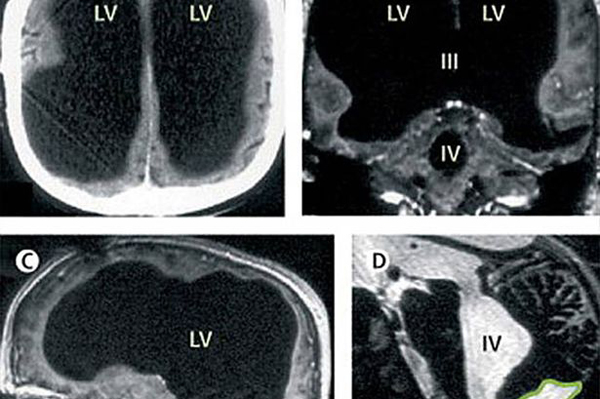

一名男子经检查发现他只剩下一般大脑

据英国《镜报》8月16日报道,近日,英国著名医学杂志《柳叶刀》刊登了一则震惊世人的医学案例,一名男子经检查发现他仅剩一半大脑,不过他仍能和其他人一样正常生活。

据悉,该男子现年44岁,是两个孩子的爸爸。早在2007年,他因为腿部疼痛前往法国一家医院检查,结果被医生告知他仅剩一半大脑。诊治他的医生利昂内尔弗耶(Lionel Feuillet)在采访中表示,该男子小时候患过脑积水,当时采用分流器进行治疗。14岁之后,分流器被取出,而脑部却持续积液,导致他的大脑大幅度萎缩,大小只有正常人的25%-50%。医学家们经过8年的研究观察,直到最近才敢确认,他的大脑通过自我重组,使其生活与常人无异。

科学家们认为,该案例说明大脑的大小与智力无关,因为当一部分脑组织萎缩坏死时,其他脑组织能够延续坏死部分的功能。